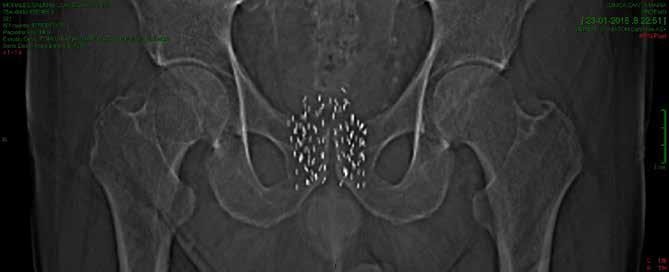

Una vez el que el paciente esté anestesiado, una grilla de metal, consistente con la grilla de la simulación computacional, se apoya en el perineo, entre el escroto y el recto, y alrededor de 20 a 25 agujas huecas muy finas se insertan a través de los agujeros de la grilla, ubicados a intervalos estratégicos. Una sonda ecográfica transrectal va guiando la distribución de las semillas, cuyo número varía entre 120 y 150. Las fuentes radioactivas se van depositando, cada una en el lugar exacto previamente calculado, mediante las agujas huecas. (Figura 1)

Un mes después de la implantación, el paciente deberá realizarse un estudio de imagen para verificar la posición de las fuentes emisoras y calcular la dosis efectiva de radiación, y así verificar que el tratamiento está funcionando de manera adecuada. (Figura 2)